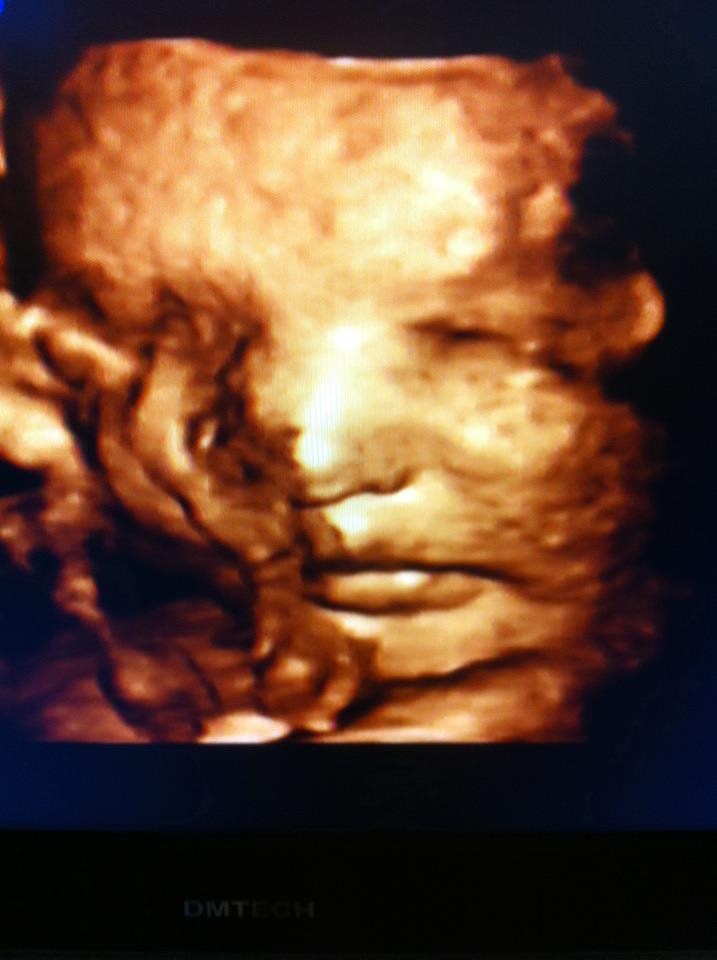

I får lige et par billeder med

vi fik nemlig lov at se ham i 3D

(det har jeg ikke prøvet før, wow en oplevelse)

1: lillebror rækker tunge